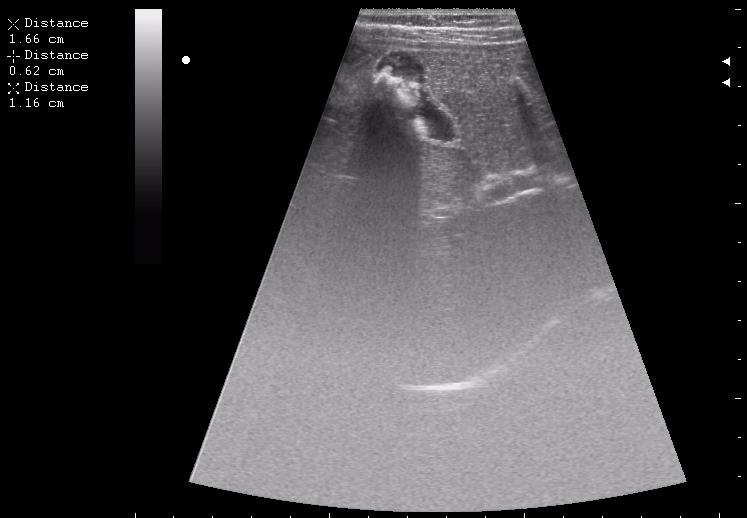

железный дрын вошел в правую подвздошную область, остановился в капсуле печени.

наезд большой черной Прады на маленькую (13кг) 5-летнюю девочку.

получает Медаксон, рабочая версия - изменение желчного пузыря вследствии травмы (шепотом - рекомендация хирургу сменить антибиотик)

сегодня был селезёночный день.